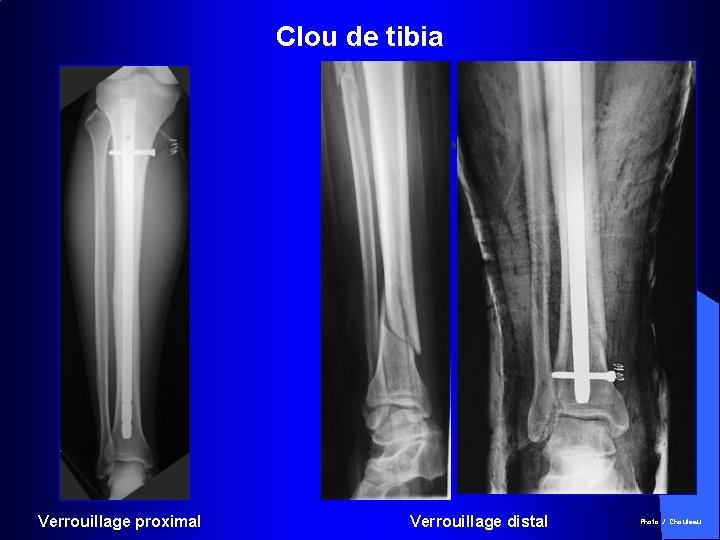

Clou de tibia Verrouillage proximal Verrouillage distal Photo J. Chouteau